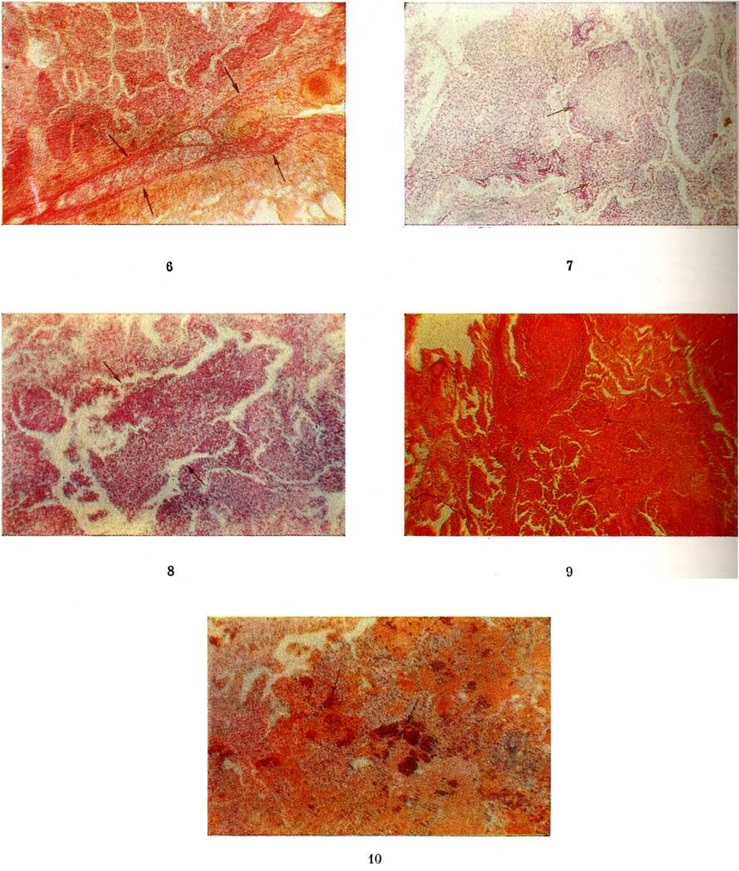

Изменения, сходные с морфологический изменениями при вирусной Пневмония, наблюдаются при микоплазменной Пневмония — респираторном микоплазмозе (смотри полный свод знаний Микоплазменные инфекции). Для неё также типично внутриклеточное размножение возбудителя (рисунок 4), хотя возможно и внеклеточное. Поражения носят характер десквамативной Пневмония при весьма умеренных макроскопических изменениях (цветной рисунок 3—5; 6—10).

Пневмомикозы (смотри полный свод знаний), в том числе кандидоз лёгких, отличаются от бактериальных Пневмония, как правило, хронический течением. В связи с этим, помимо острых воспалительных изменений лёгких, напоминающих бактериальные, наблюдается образование инфекционные гранулем (смотри полный свод знаний Гранулема).

Пневмоцистная Пневмония (смотри полный свод знаний Пневмоцистоз) отличается от всех других Пневмония скоплением большого количества возбудителей в альвеолах при отсутствии экссудативной реакции и более выраженной, преимущественно плазмоцитарной инфильтрацией межуточной ткани.